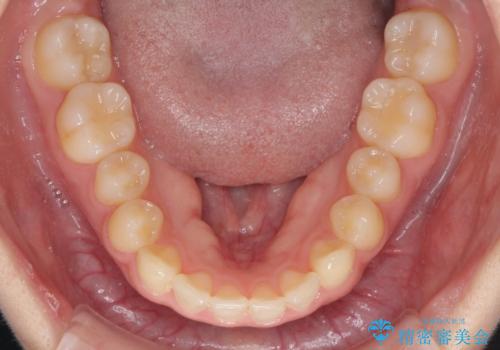

気になる残存乳歯と八重歯 ワイヤー矯正を併用したインビザライン治療

- 八重歯を気にして来院された患者様です。

八重歯のために乳歯が残存していたため、乳歯を抜去して八重歯となっている犬歯を歯列に収めることとしました。

八重歯の移動量が多くなるため、インビザラインと併用してワイヤー矯正を行い、八重歯を改善した後に、上下歯列をインビザラインで整えることとしました。

犬歯は歯根が長くて太いため移動に時間がかかる上に、周囲の歯が八重歯に寄ってきてしまうため、仕上がるまでに期間がかかりました。